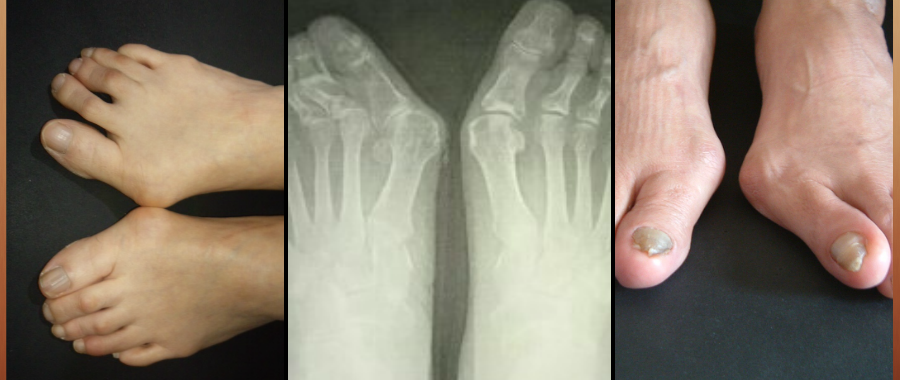

外反母趾やお困り、悩みの緩和、解消のための靴を造ります。

外反母趾の害は

外反母趾だけに止まりません。

靴の危険、リスクを正しく知らなければ

正しい靴選びへ進めません。